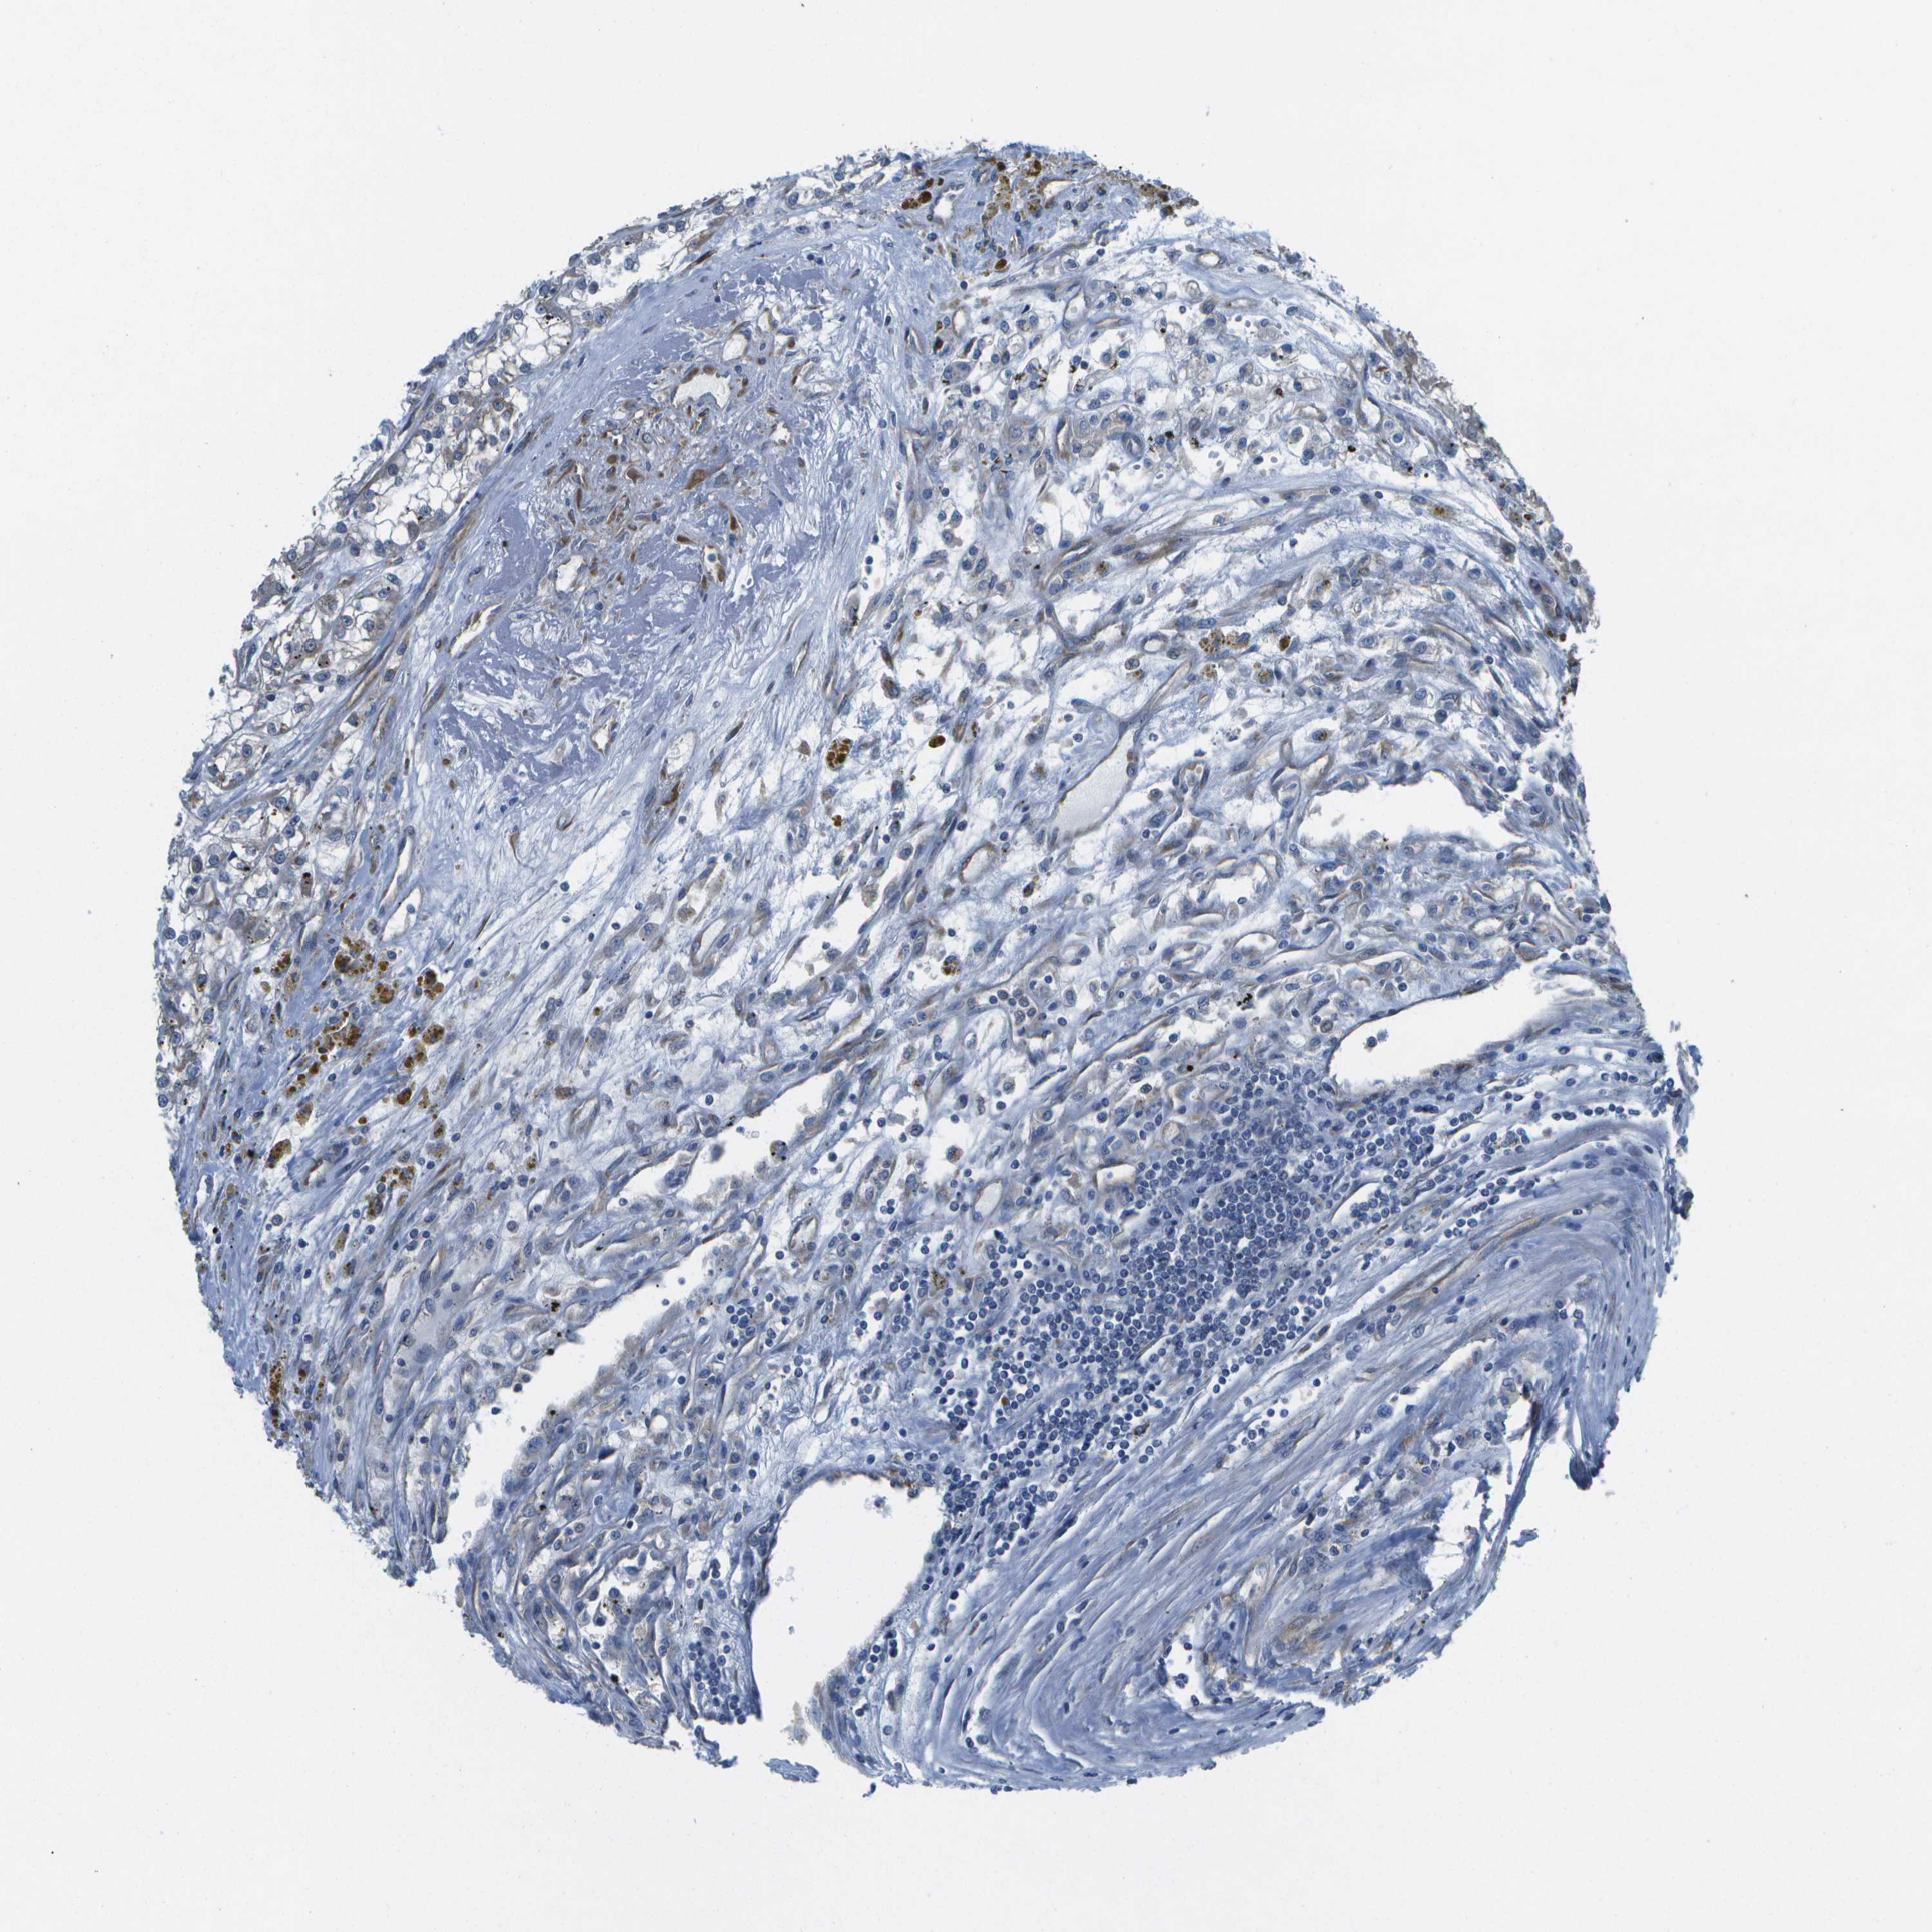

CANCER RENAL CANCER Show tissue menu

KICH TCGA KIRC TCGA KIRC VALIDATION KIRP TCGA PROTEIN RCC CPTAC PROTEIN EXPRESSION